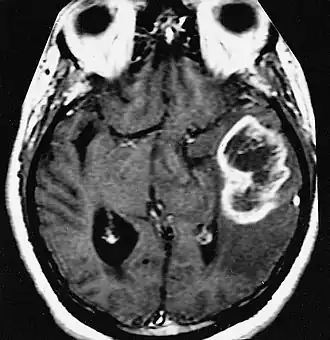

En las imágenes de TC y RM se muestra como una lesión heterogénea, de contorno irregular, que capta contraste en anillo y con un área central necrótica.

Diagnóstico por imagen y glioblastoma

La TC muestra una lesión de morfología irregular, predominantemente hipodensa y fuertemente dishomogénea, debido a la presencia de grandes áreas necróticas de más clara hipodensidad y de áreas sólidas hiperdensas. Estas últimas son la expresión de un rápido crecimiento y por lo tanto de una elevada malignidad. Son frecuentes las zonas hemorrágicas, que van desde pequeños focos a grandes áreas hemáticas que pueden cubrir toda la lesión. Es característica la morfología en "mariposa" si el tumor se asienta en ambos hemisferios a través del cuerpo calloso.

Tras la aplicación de contraste aparecen gruesos anillos alrededor de las áreas necróticas. En la RM, la parte sólida aparece hipointensa en T1 e hiperintensa en T2 con zonas de señal más elevada en las partes de mayor celularidad. Las áreas necróticas, hiperintensas en T2, pueden presentarse hipo-, iso- o hiperintensas en T1 en función del contenido proteico o de productos de la degradación de la hemoglobina. El realce tras el contraste suele ser intenso e irregular en la periferia del tumor e identifica sobre todo la componente celular "proliferativa" de la neoplasia. Son comunes las áreas puntiformes y serpiginosas de ausencia de señal de flujo, asociadas a la presencia de una neovascularización rica. Estos vasos de neoformación patológica carecen de barrera hematoencefálica, lo que explica tanto la abundante impregnación como el edema vasogénico perilesional (véase la sección anterior), debido al paso de líquido al medio extracelular.[72][73]